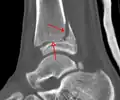

Fracture of both sides of the ankle with dislocation as seen on anteroposterior X-ray. (1) fibula, (2) tibia, (arrow) medial malleolus, (arrowhead) lateral malleolus